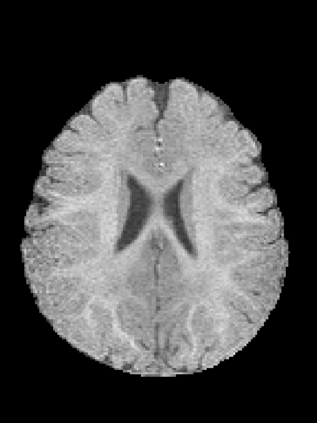

An important step in early brain development study is to perform automatic segmentation of infant brain magnetic resonance (MR) images into cerebrospinal fluid (CSF), gray matter (GM) and white matter (WM) regions. This task is especially challenging in the isointense stage (approximately 6-8 months of age) when GM and WM exhibit similar levels of intensities in MR images. Deep learning has shown its great promise in various image segmentation tasks. However, existing models do not have an efficient and effective way to aggregate global information. They also suffer from information loss during up-sampling operations. In this work, we address these problems by proposing a global aggregation block, which can be flexibly used for global information fusion. We build a novel model based on 3D U-Net to make fast and accurate voxel-wise dense prediction. We perform thorough experiments, and results indicate that our model outperforms previous best models significantly on 3D multimodality isointense infant brain MR image segmentation.